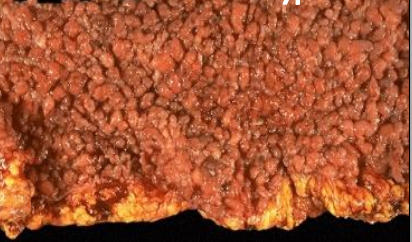

Colorectal Polyps seen in Gardner Syndrome

Pano of patient with gardner syndrome